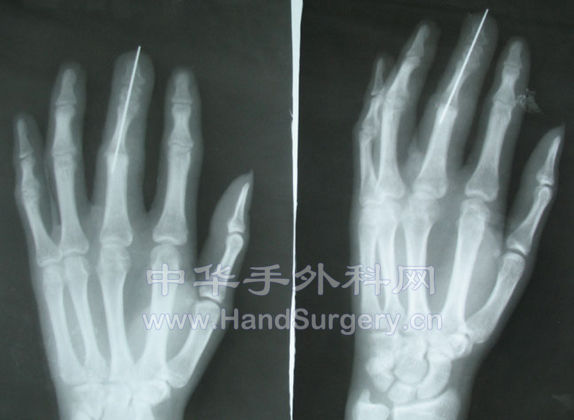

术后的X线片

X线.jpg

关节融合了,近指间关节前移了。这种四度缺损再造术后功能不理想。

大家讨论2-5指4度缺损足趾移植再造术后近指间关节前移手外科有什么进展。